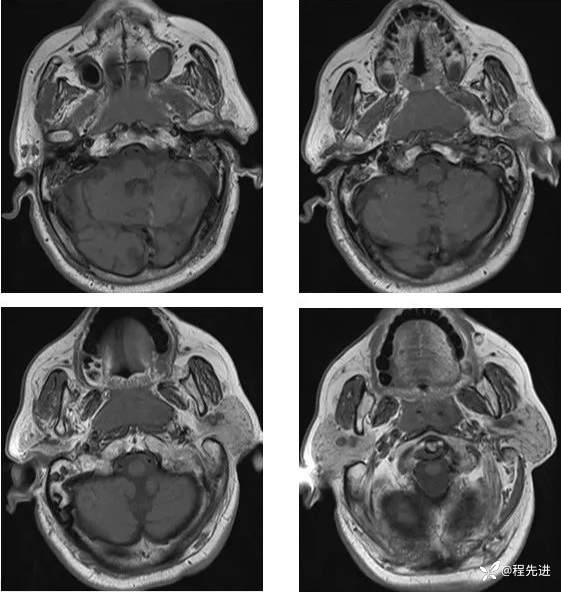

MR平扫+增强:

T1增强: